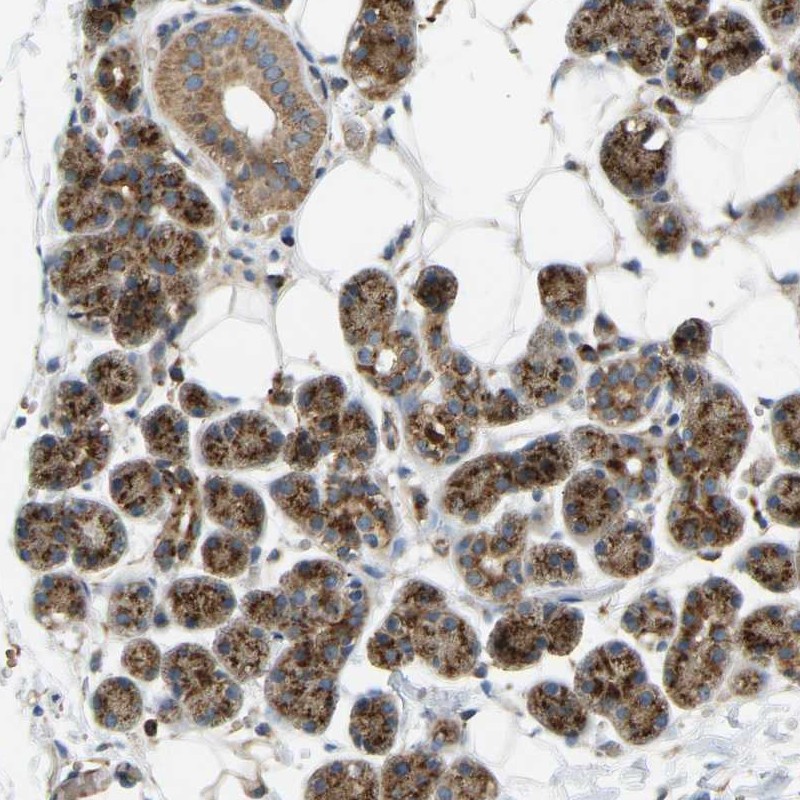

Immunohistochemical staining of human salivary gland shows strong granular cytoplasmic positivity in glandular cells.